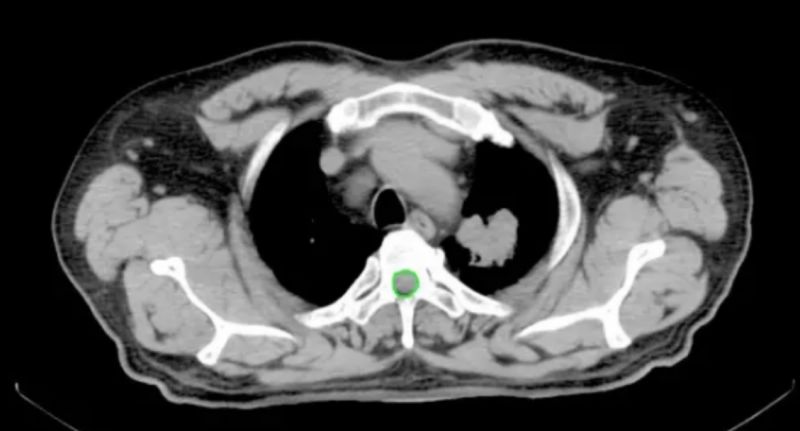

质子治疗肺鳞癌一个月后肿瘤缩小65%

患者:男,55岁

PET-CT显示:左肺上叶尖后段肺癌;并右侧顶叶脑转移,考虑为“肺癌脑转移”。拟行手术治疗,因肺部肿瘤靠近大血管,不能手术,经专家咨询,行质子放射治疗。本案例经质子治疗一个月后,肿瘤体积缩小65%,肿瘤负荷大大降低,症状明显改善,生活质量未受任何影响。

治疗前最大截面:3.88×3.90,体积由44.56cm3;治疗一个月后截面为2.48×2.13,体积15.68cm3;体积缩小65%